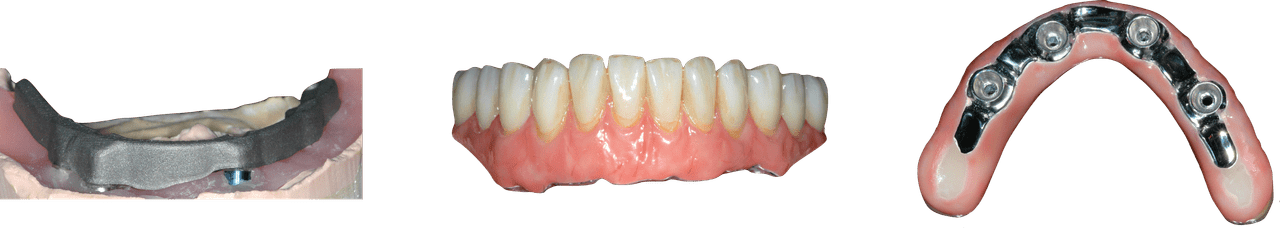

Ce cours de niveau maîtrise aborde à la fois la prévention et la gestion des complications chirurgicales et restauratrices. Dans le domaine chirurgical, la présentation se concentre sur l’échec précoce de l’implant et la maladie péri-implantaire ultérieure. Les concepts prothétiques comprendront la conception de prothèses préventives, le retrait des vis/piliers et un séquençage qui reconnaît l’importance de l’expérience du patient.

Le programme consacré à l’implantologie est une série de cours interactifs basés sur les procédures qui utilisent des cas individuels pour enseigner le traitement actuel des implants. Cette approche est contraire à l’éducation dentaire conventionnelle qui se concentre davantage sur les sujets et la théorie didactiques. L’objectif de cette approche pédagogique est de mettre en évidence les patients et les procédures rencontrés dans la pratique clinique quotidienne, où les concepts les plus importants sont observés et discutés dans de multiples scénarios cliniques.